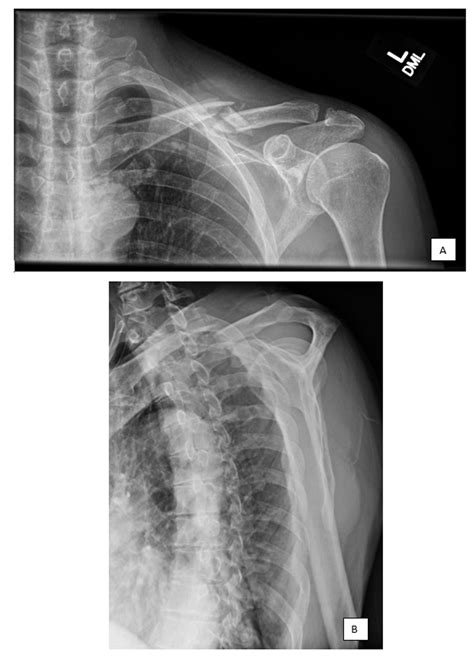

Diagnosing a fracture involves a combination of physical examination and imaging tests. The healthcare provider will assess the injury site for pain, swelling, and deformity. Imaging tests, such as X-rays, CT scans, or MRI, are used to confirm the diagnosis and determine the type and severity of the fracture.

X-rays are the most common imaging test used to diagnose fractures. They provide a clear view of the bone structure and can show whether the fracture is displaced or nondisplaced. CT scans and MRI may be used for more detailed imaging, especially in complex fractures or when soft tissue damage is suspected.